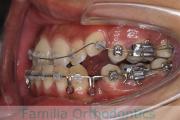

- ≫治療中 ステップ1

上顎

下顎

- ≫治療後